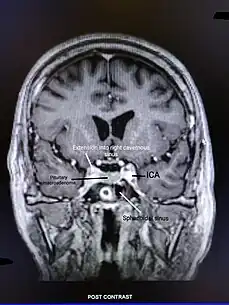

T1-weighted post contrast coronal section of non-functioning pituitary adenoma. The tumor is seen extending into the right cavernous sinus.

All age groups are susceptible to misclassification of an adrenal crisis diagnosis,[7] but older patients may be more vulnerable if relative hypotension is not evaluated, given the age-related rise in blood pressure.[58] It is possible to confuse hyponatremia—a common sign of adrenal insufficiency or adrenal crisis—with the syndrome of inappropriate antidiuretic hormone secretion, which is frequently brought on by disease, drugs, or aging itself.[59]

The treatment of pituitary tumors and the widespread use of opioids for both malignant and increasingly non-malignant pain, as well as exogenous glucocorticoid therapy for the numerous inflammatory as well as malignant conditions that become more common in people over 60, are the main causes of a new diagnosis of adrenal insufficiency in older adults.[60][57] Adrenal crisis is more likely to occur in older people.[61] Urinary tract infections, particularly in older women, are often linked to an adrenal crisis, as is pneumonia as well as a flare-up of chronic respiratory disease.[62] Cellulitis is linked to adrenal crises within this age range and may be more prevalent in patients with fragile skin who have been exposed to higher doses of glucocorticoids.[63] Older adults frequently experience falls and fractures, which may be linked to postural hypotension, especially in those who have primary adrenal insufficiency.[64]